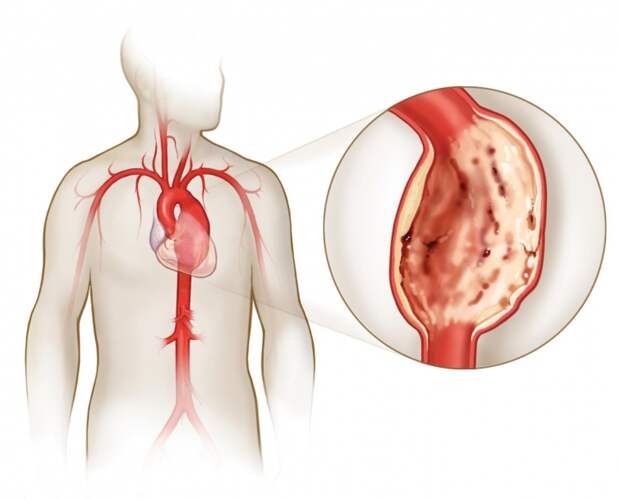

Аневризм, или расширение сосуда может убить вас совершенно неожиданно в течение нескольких секунд. Даже если вы молоды и здоровы